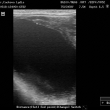

ultrasonografické vyšetření klisny